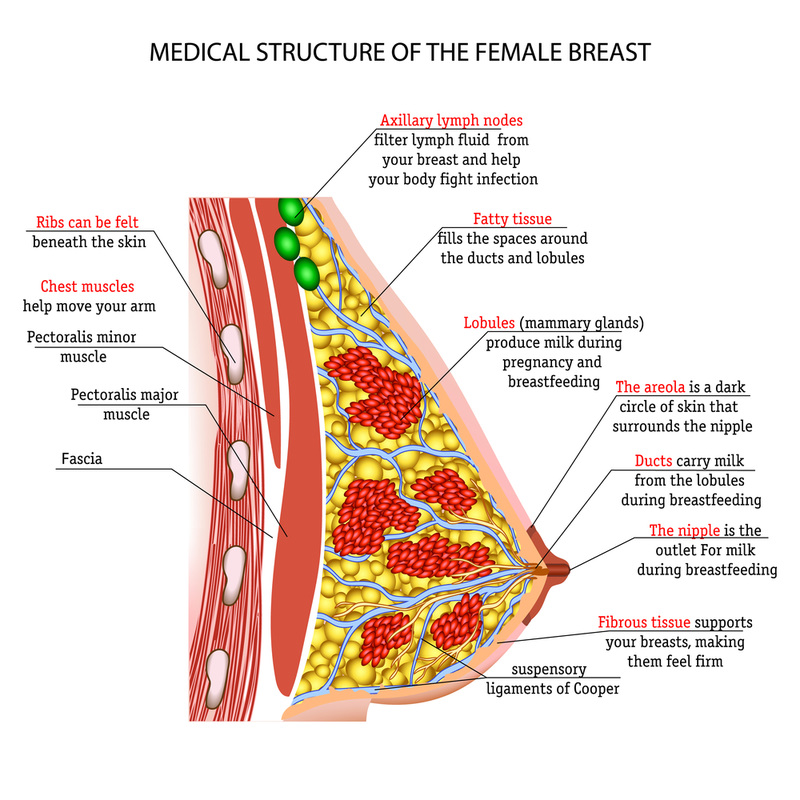

Breast Tissue Anatomy Physiology 101 JACKIE BELL NATURAL HEALTH

Breast Human Anatomy

Anatomy and physiology of the breast Philips Healthcare